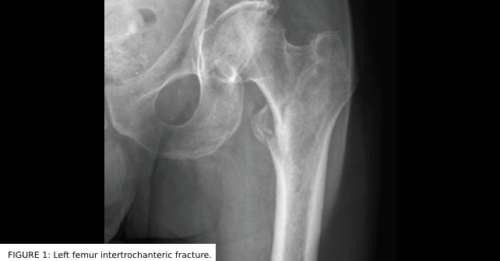

A 77-year-old man presented to the emergency department (ED) with hip pain following a fall. On ED…